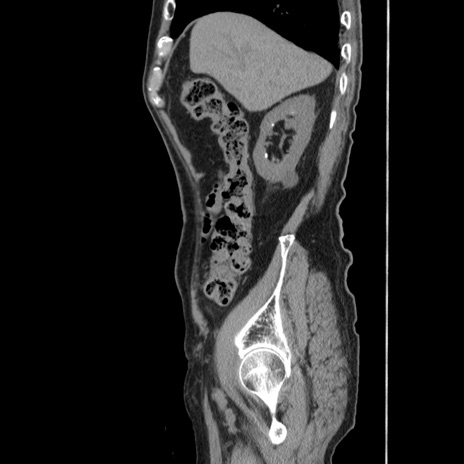

症例24(矢状断像)

【症例】80歳代男性

【主訴】左側腹部痛、嘔吐

【現病歴】本日早朝より左腹部に痛みあり。昼頃嘔吐認めたため、救急要請。

【既往歴】直腸癌(Mile手術)、胆摘

【身体所見】意識清明、BT 35.9℃、BP 221/93mmHg、SpO2 97%(RA) 、腹部:左ストーマ周囲に限局性の腹部膨隆あり。 膨隆部自発痛・圧痛あり・軟。

【データ】WBC 7700、CRP 0.09